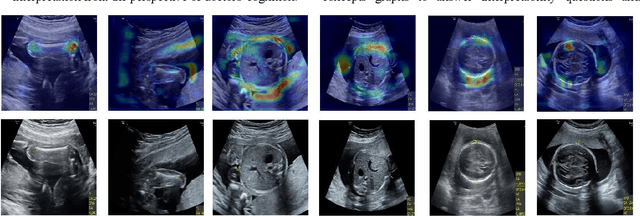

Abstract:Although deep neural networks (DNN) have achieved state-of-the-art performance in various fields, some unexpected errors are often found in the neural network, which is very dangerous for some tasks requiring high reliability and high security.The non-transparency and unexplainably of CNN still limit its application in many fields, such as medical care and finance. Despite current studies that have been committed to visualizing the decision process of DNN, most of these methods focus on the low level and do not take into account the prior knowledge of medicine.In this work, we propose an interpretable framework based on key medical concepts, enabling CNN to explain from the perspective of doctors' cognition.We propose an interpretable automatic recognition framework for the ultrasonic standard plane, which uses a concept-based graph convolutional neural network to construct the relationships between key medical concepts, to obtain an interpretation consistent with a doctor's cognition.